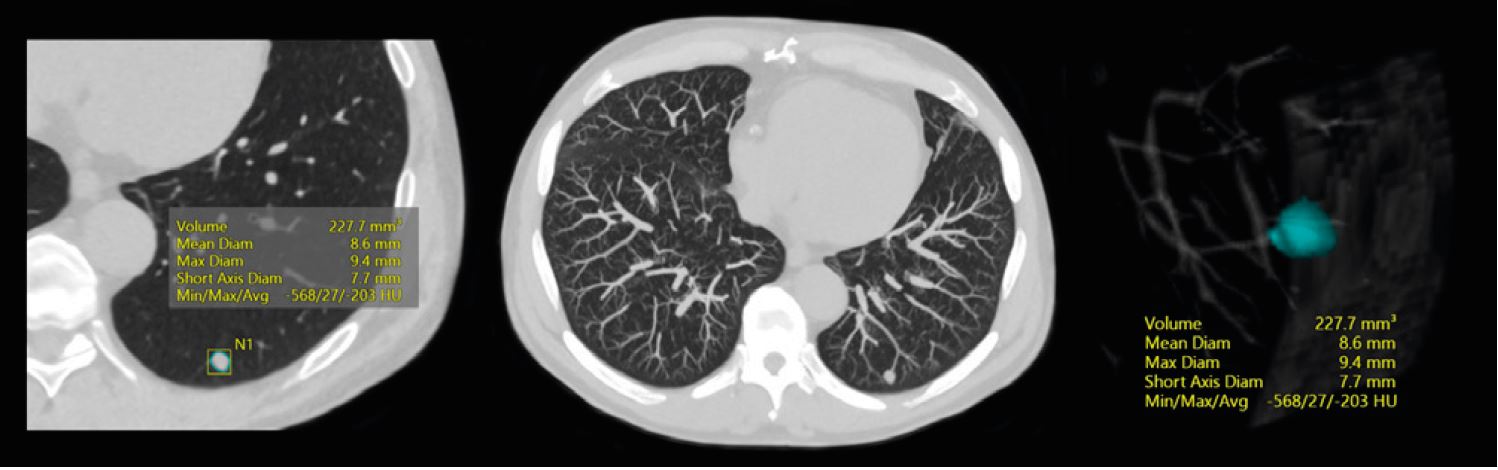

Скринінг легень

Рак легень є однією з головних причин смертності від онкології у всьому світі. Його раннє виявлення за допомогою КТ з низькою дозою дає змогу призначити раннє лікування та кращий прогноз. Однак найбільше занепокоєння при скринінгу легень за допомогою КТ викликає доза, а по- друге, як організації охорони здоров’я можуть інтегрувати додаткову

пропускну здатність великої кількості кандидатів на скринінг. Окрім забезпечення високої пропускної здатності, Aquilion Serve SP має функцію SilverBeam, яка змінює правила гри у візуалізації легень на низьких дозах.

Фільтр SilverBeam від Canon Medical у поєднанні з INSTINX і реконструкція із штучним інтелектом для КТ забезпечує зниження дози опромінення, збільшення пропускної здатності пацієнтів, покращену якість дослідження з мінімальним шумом зображення, зберігаючи загальну якість та точність діагностики.

Одиночний легеневий вузлик із вимірюванням об’єму.